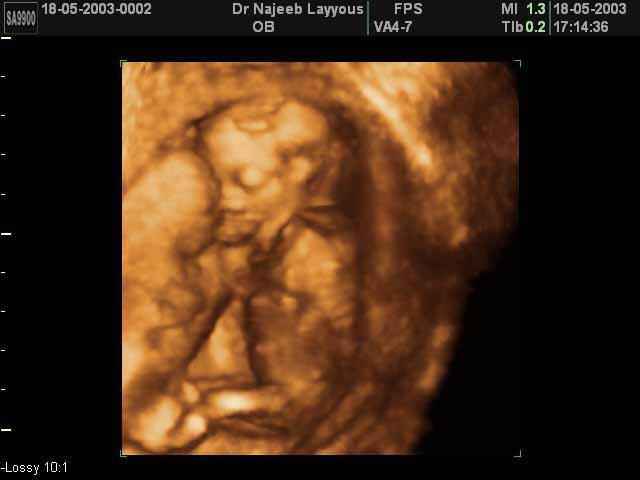

- Fetal Behavior Ultrasound Photos